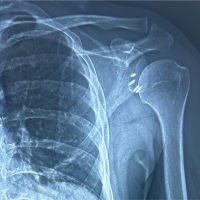

The patient was managed acutely on the slope and in our emergency room, according to ATLS principles, with a presenting GCS of 10 – E3V3M4. Full clinical examination was supplemented with imaging including a FAST scan and radiographs of shoulder joints, thorax, and pelvis. These confirmed the clinically suspected bilateral anterior shoulder dislocation combined with a four-part proximal humerus fracture on the left side and an osseous rotator cuff avulsion on the right side. The patient was neurovascular intact (Fig. 1, 2a and 3a).